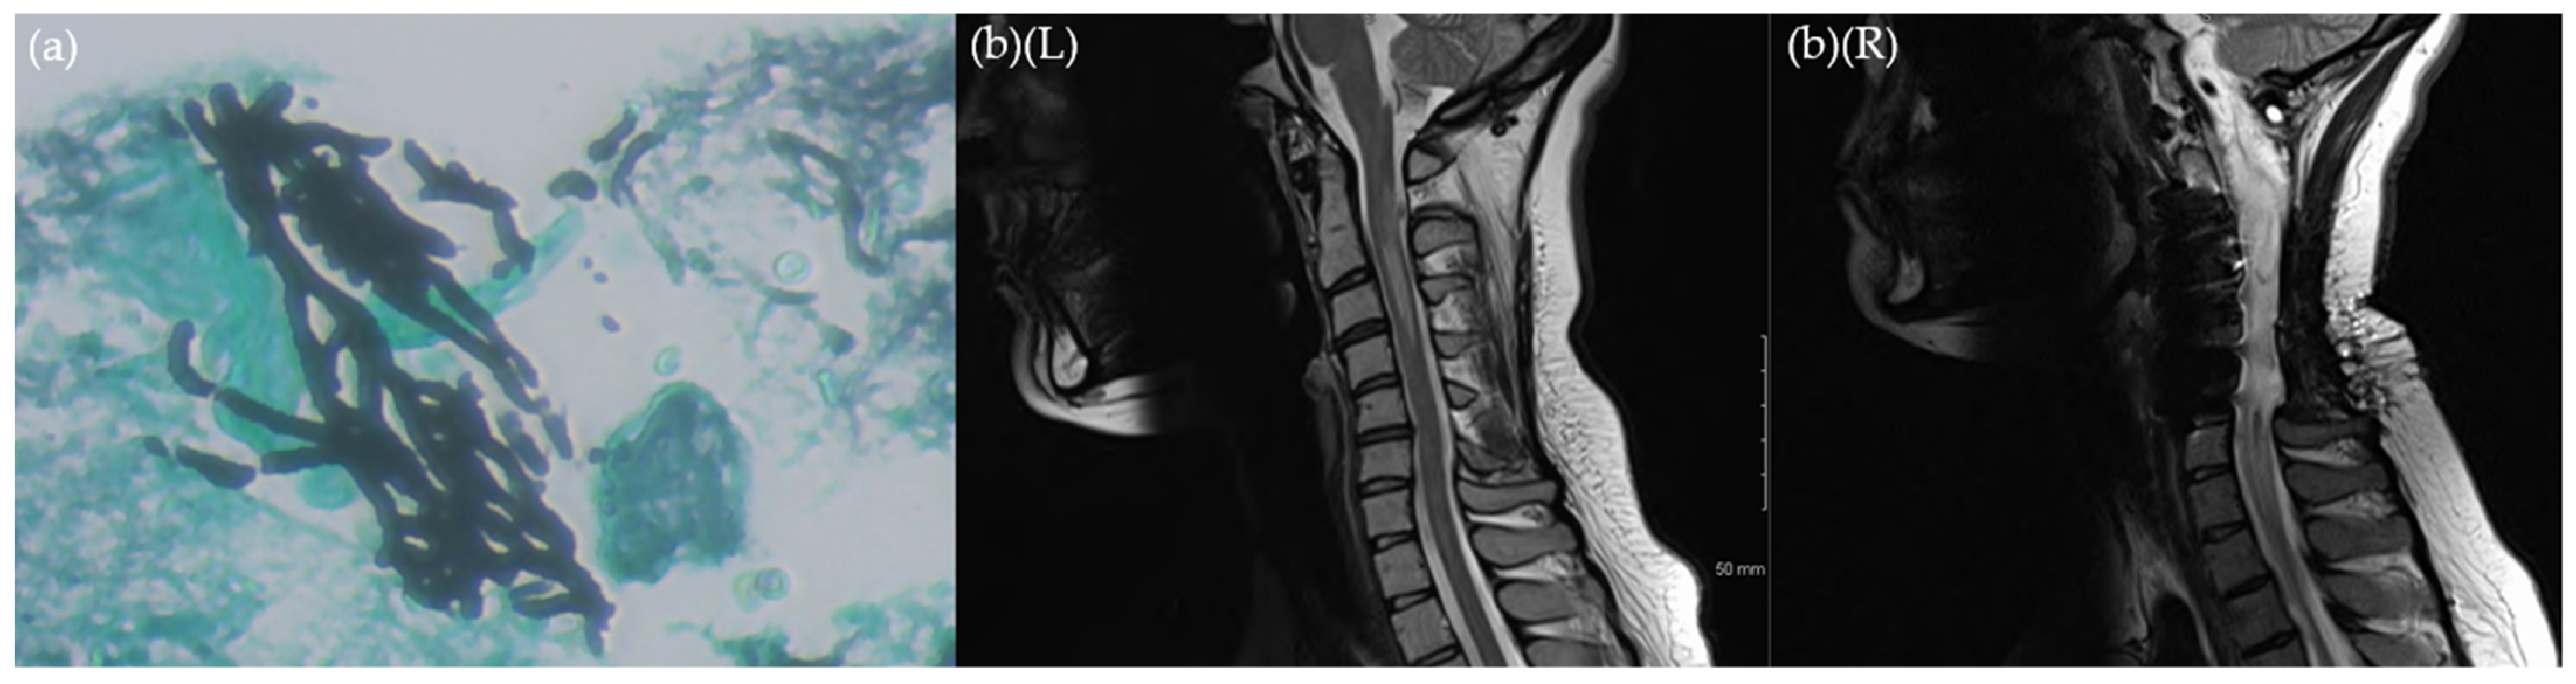

Isavuconazole Treatment of Spinal Cord Invasive Aspergillosis Guided by Cerebrospinal Fluid (1,3)-β-d-Glucan Levels in a Patient with Low Interferon-Gamma and Ulcerative Colitis

2. Case